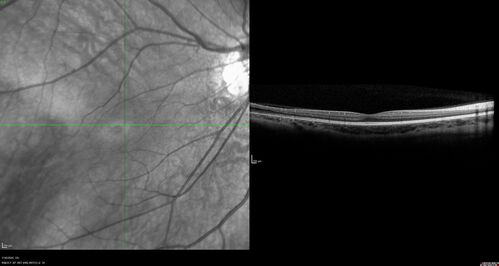

Familial Exudative Vitreoretinopathy - FEVR - Stage 1-b both eyes

She was born at term.   No family history of eye disease.

VA OD: Dcc20/25, VA OS: Dcc20/200+1 Ncc20/400

Anterior segment normal – clear lenses